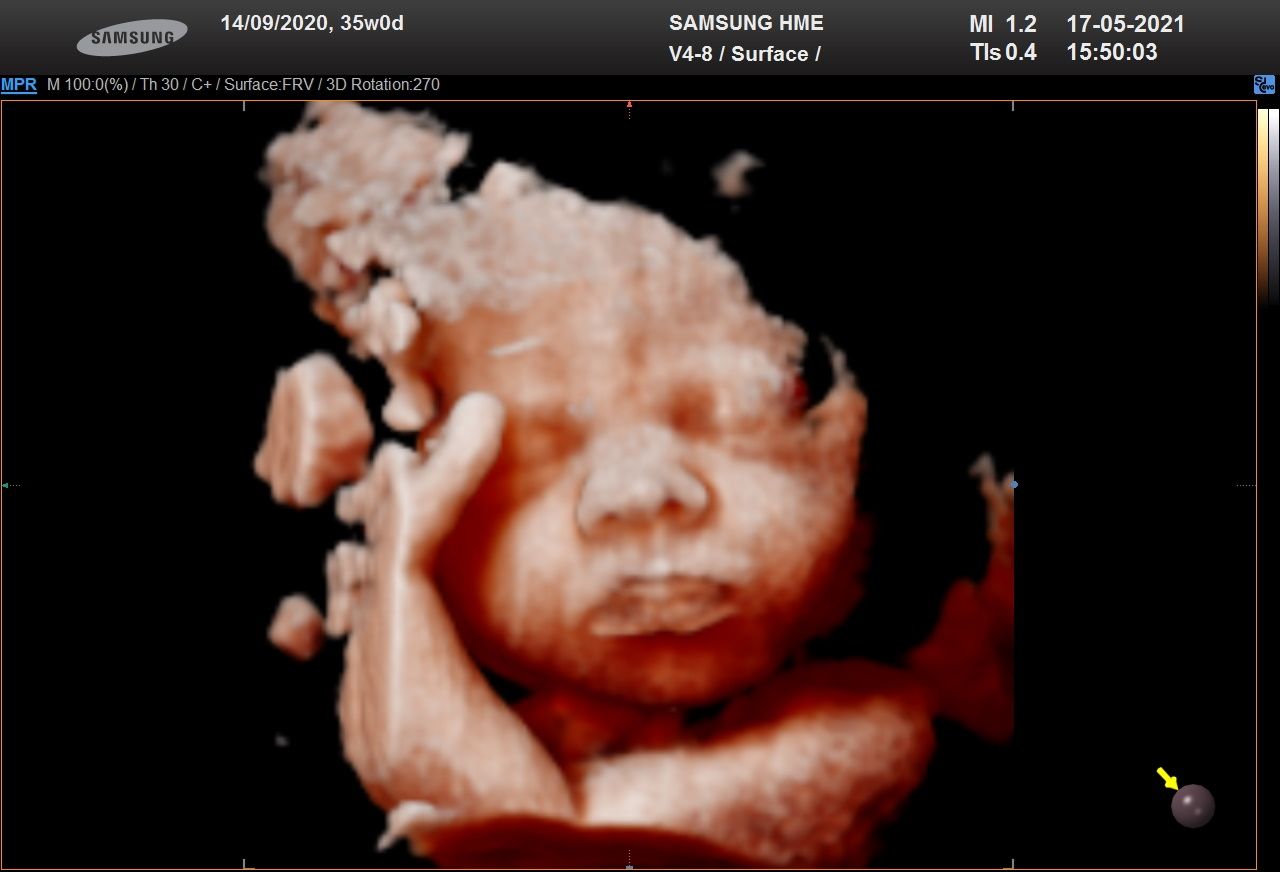

Foto e video